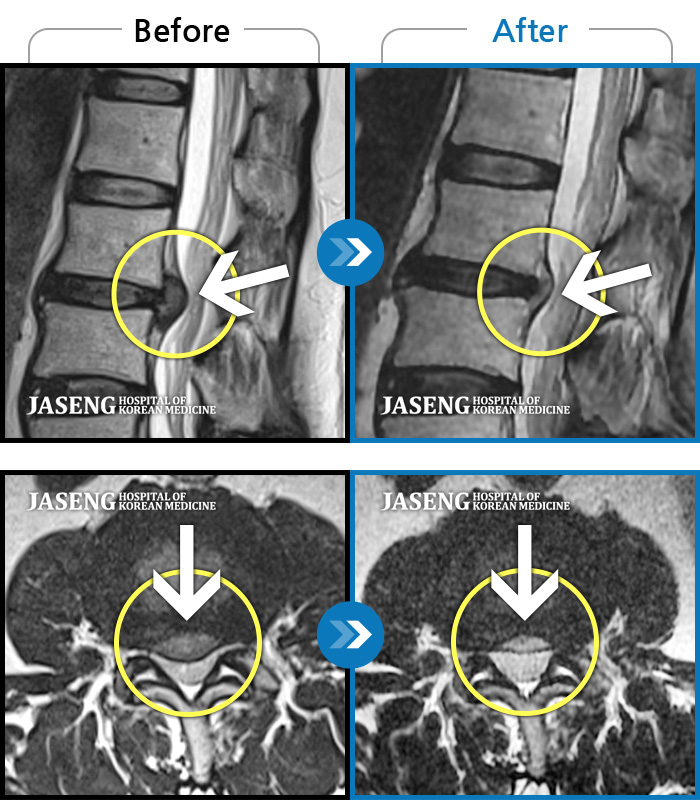

24년 3월 디스크파열 진단받고 극심한 통증으로 입원하여 김재영원장님께 치료받은 후 증상이 매우 호전되어 퇴원한 경험이 있습니다. 원장님께서 퇴원무렵 컨디션 관리를 엄청 당부하셨지만 근무하는 과정에서 발생하는 어쩔수 없는 과로와 극심한 스트레스는 서서이 좋아지던 저의 디스크 통증을 급기야 재발하게 만들었습니다. 7월말 다시 시작된 왼쪽 종아리와 발가락으로 퍼지는 심한 통증과 몸살로 더이상 근무를 계속할수 없어서 급하게 원장님을 뵙고 입원 치료하게 되었습니다. 김재영 원장님께 진료받고 극심했던 방사통이 진통제 없이 생활하기 까지 호전된 경험이 있고 원장님께서도 저의 상황을 어느정도 아시고 계셔서 이번에는 처음 디스크 터졌을때처럼 엄청 겁먹지 않고 원장님께 사소한 증상 하나하나 말씀드리면서 차분하게 치료받을 수 있었습니다. 제가 직장다니면서 힘든 마음으로 다시 입원하게 된 상황을 이해해 주시고 치료가 빠르게 될수 있도록 매일 소소한 증상 하나하나 신경쓰셔서 치료해주시고자 애써 주셔서 진심으로 감사했습니다. 심한 몸살이 디스크 통증과 함께 와서 소화도 안되고 기운도 없이 입원 첫주 무척 힘든 시간을 보냈습니다. 원장님께서는 소화가 잘 되게 침치료도 병행해 주시고, 소화제 종류도 다양하게 바꿔가며 저의 컨디션이 되돌아 올수 있게 처방을 해 주셨습니다. 무수히 많은 환자를 진료하시는 바쁘신 진료시간 중에서도 저의 증상을 매일 편하게 말씀 드릴수 있게 대해 주셔서 소소한 증상까지 말씀 드려 본의 아니게 원장님을 피곤하게 해드렸습니다. 입원 9일차 정도되니 그렇게 아팠던 종아리 통증은 거의 사라지고 소화기능도 조금씩 회복되고 있습니다. 통원치료때도, 입원치료때도 늘 한결같이 저의 증상을 귀담아 들어주시고 치료가 빠르게 될수 있도록 애써 주셔서 고맙습니다. 침 치료시에 어쩔수 없이 듣게 되는 다른 환자분들과 원장님과의 대화속에서도 치료받으시는 어버님 아버님들께서 원장님께 아픈 곳을 편히 말씀하시는것이 느껴졌습니다. 원장님께서도 일일이 다 성의껏 어르신들 말씀 귀담아 들어주시고 치료해 주시는것을 보니 원장님께서는 참으로 인품마저 다정하신 분 같았습니다. 거기에 아픈 통증도 꼭꼭 잡아주시니 원장님께 진료받는 많은 환자들이 원장님의 마음에 심적으로 안정을 받으시고 원장님의 전문적인 의료 도움을 크게 받는것 같습니다. 원장님께서 환자를 대해 주시는 따뜻함, 실력있는 의술 덕분에 제가 입원하는 기간 마음 편하게 치료 받을수 있었습니다. 통증이 자주 재발하면 완치되기가 힘드니 조심해야 된다는 원장님 조언 잘 새겨듣고 올 하반기에는 다시 입원하지 않도록 노력해 보겠습니다. ^^ 원장님께서도 남은 여름 건강 잘 챙기세요~~~ 고맙습니다. 김재영 원장님 ^^

저는 허리디스크 파열로 3월 1일부터 입원하여 3주째 해운대 자생 김재영 원장님께 입원진료를 받고 있습니다.

이번주에 퇴원할 예정이라 그동안 원장님께 진료 받고 조금씩 나이지고 있는 부분에 대해 진심으로 감사한 마음을 전하고 싶습니다.

허리 디스크 파열이라는 사실을 모르고 단순하게 허리디스크가 조금 튀어나왔을거라고 생각하고 이전 교통사고로 생긴 두통 치료를 김재영 원장님께 진료받고 나은 기억이 있어 혹시나 하여 원장님과 상담을 했습니다.

김재영 원장님께서 혹시 모르니 그래도 MRI를 찍어보고 정확히 원인을 알고 치료를 하자고 권유하셔서 MRI를 찍게 되었습니다. 결과는 디스크 파열로 심각한 상황이었습니다.

결과를 보시고 원장님은 한방 치료에 대한 막연한 희망을 주시기 보다는 정확한 저의 상황에 대해 설명해 주셨고 제가 어떤 방향을 원하는지 귀담아 주셨습니다.

저는 수술이 당장 시급한, risk가 상당히 있는 MRI 결과였지만 갑작스러운 결과에 수술을 바로 하기엔 너무 겁이 나서 일단 입원하여 원장님 치료를 받아보기로 마음먹고 바로 입원했습니다.

지옥같은 1주일이 지나고 아주 조금씩 방사통이 약해지기 시작했고 지금 입원 3주차에 접어들어서는 그렇게 심했던 방사통은 낮에 근무가 가능할 정도로 호전되었습니다.